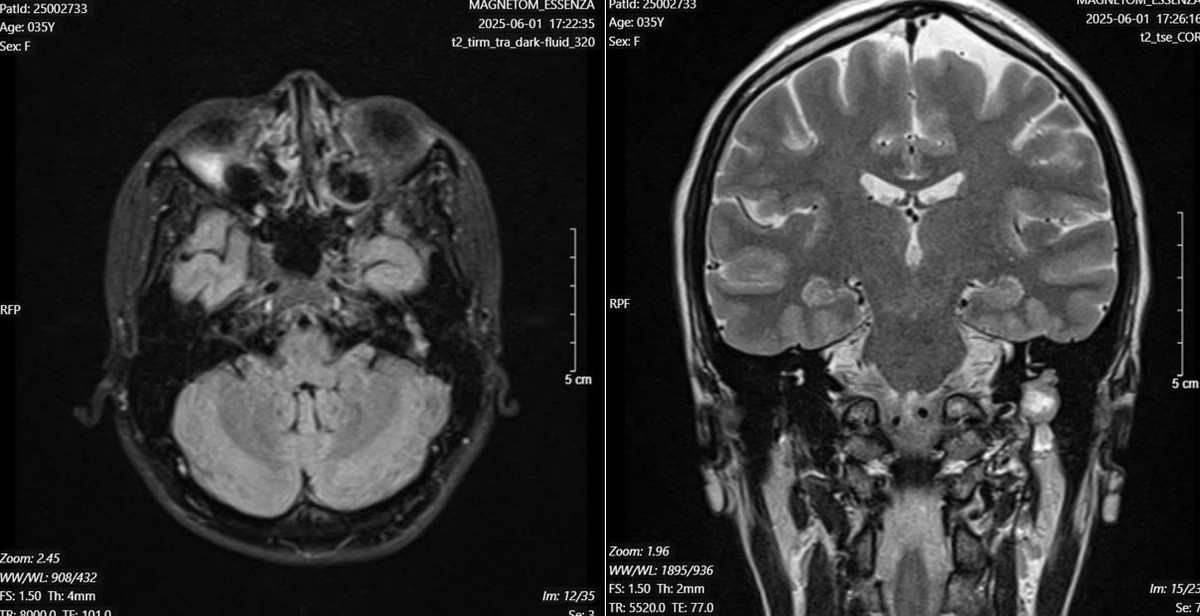

Tại đây, các bác sĩ đã tiến hành nội soi tai, phát hiện khối màu hồng ở phía sau màng nhĩ. Hình ảnh trên cắt lớp vi tính và cộng hưởng từ (MRI) cho thấy một khối u lớn ở đoạn II và III dây thần kinh mặt – nguyên nhân gây liệt mặt kéo dài suốt nhiều năm.

Hình ảnh chụp cộng hưởng từ gợi ý u dây thần kinh mặt - Ảnh BVCC

Ca phẫu thuật diễn ra thuận lợi, kết quả giải phẫu bệnh khối u sau phẫu thuật là u tế bào Schwann – một khối u lành tính, hiếm gặp của dây thần kinh mặt.